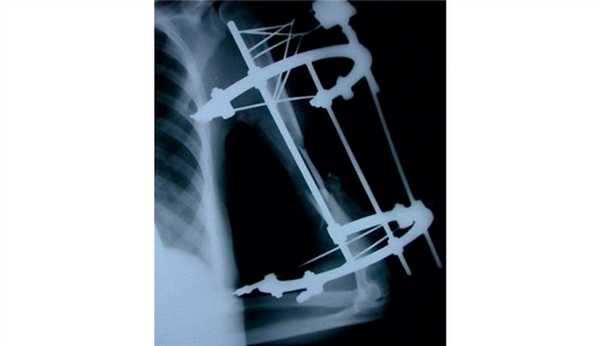

После консолидации перелома через 71 день произведен демонтаж аппарата (рис. 5). Рисунок 5. Рентгенограммы больной П. после остеосинтеза левой плечевой кости спице-стержневым аппаратом. Движения в левом локтевом суставе после демонтажа аппарата от 0 до 128° (рис. 6). Рисунок 6. Внешний вид больной П. после демонтажа аппарата (объем движений в левом локтевом суставе от 0 до 128°).